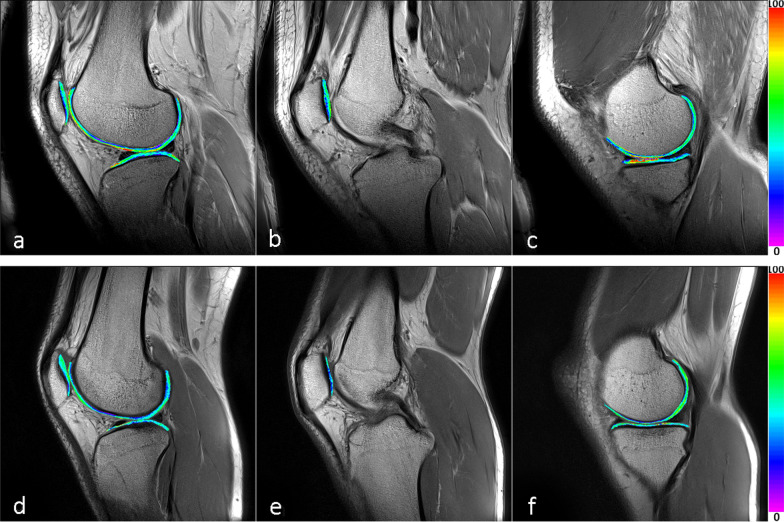

The T2 data demonstrated that nine subregions expressed statistically significant increase in the T2 values of the case group: MPs (P1 = 0.002), LPs (P1 = 0.015), MFas (P1 = 0.036), MFcd (P1 = 0.015), MFcs (P1 = 0.000), MFps (P1 = 0.021), LFas (P1 = 0.005), LFcs (P1 = 0.000) and MTcs (P1 = 0.011). There were five subregions in the case group with age ≤ 35 years: MPs (P2 = 0.009), LPs (P2 = 0.028), MFcs (P2 = 0.002), LFcs (P2 = 0.003) and MTcs (P2 = 0.018). In addition, the differences were more significant in the femur and patella regions. The data showed a significant difference in only one subregion of the tibia (Tables 2 and 4). We also showed the T2 maps of cartilage from one patient and one volunteer (Fig. 3).

Fig. 3.

T2 maps of the right knee cartilage from a 26-year-old male patient (a–c) and the right knee cartilage from an 18-year-old male volunteer (d–f). a and d illustrate the lateral cartilage of tibiofemoral joint and patellofemoral joint. b, c and e, f illustrate the medial cartilage of the tibiofemoral joint and patellofemoral joint. The color scale is shown on the right